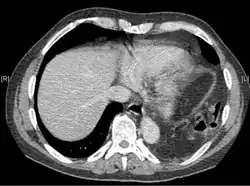

Exames físicos não são confiáveis, pois geralmente não há sinais físicos específicos para diagnosticar essa condição.[3] Métodos toracoscópicos e laparoscópicos podem ser precisos.[12] A radiografia de tórax é conhecida por ser pouco confiável no diagnóstico de ruptura do diafragma;[4] ela apresenta baixa sensibilidade e especificidade para a lesão.[5] Frequentemente, outra lesão, como contusão pulmonar, mascara a lesão na radiografia.[6] Em metade dos casos, as radiografias iniciais são normais; na maioria dos casos anormais, há hemotórax ou pneumotórax.[4] Uma sonda nasogástrica do estômago pode aparecer na cavidade torácica na radiografia; esse sinal é patognomônico [en] para ruptura do diafragma, mas é raro.[4] A radiografia é mais eficaz para detectar a lesão quando realizada de trás com o paciente em pé, mas isso geralmente não é possível, pois o paciente costuma estar instável; assim, é feita de frente com o paciente deitado.[5] A ventilação com pressão positiva ajuda a impedir a herniação dos órgãos abdominais para a cavidade torácica, mas também pode dificultar a detecção da lesão na radiografia.[4]

A tomografia computadorizada tem maior precisão diagnóstica que a radiografia,[7] mas não há achados específicos na tomografia que confirmem o diagnóstico.[9] A borda livre de um diafragma rompido pode se enrolar e ficar perpendicular à parede torácica, um sinal conhecido como diafragma pendente. Um órgão herniado pode se contrair no local da ruptura, um sinal chamado de sinal do colar. Se o fígado hernia através de uma ruptura à direita, pode produzir dois sinais conhecidos como sinal da corcova e sinal da banda. O sinal da corcova é uma forma do sinal do colar à direita. O sinal da banda é uma linha brilhante que atravessa o fígado, acreditada como resultante da compressão pelo diafragma rompido.[13] Embora a tomografia aumente as chances de diagnóstico pré-cirúrgico de ruptura do diafragma, a taxa de diagnóstico antes da cirurgia ainda é de apenas 31–43,5%.[7] Outro método diagnóstico é a laparotomia, mas ela falha em detectar rupturas do diafragma em até 15% dos casos.[4] Frequentemente, a lesão do diafragma é descoberta durante uma laparotomia realizada por outra lesão abdominal.[4] Como as laparotomias são mais comuns em traumas penetrantes do que em traumas contusos, a ruptura do diafragma é encontrada com maior frequência nesses casos.[14] A toracoscopia é mais confiável para detectar rupturas do diafragma do que a laparotomia e é especialmente útil quando se suspeita de hérnia diafragmática crônica.[4]

Localização